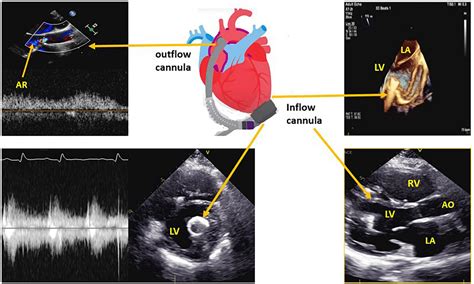

The LVAD is a marvel of modern biomedical engineering. It consists of several key components that work in harmony to sustain circulation. The pump itself is connected to the left ventricle, drawing oxygen-rich blood from the heart and pushing it into the aorta, the body’s main artery. This bypasses the weakened chamber and ensures that vital organs, such as the brain and kidneys, receive the oxygenated blood they require.